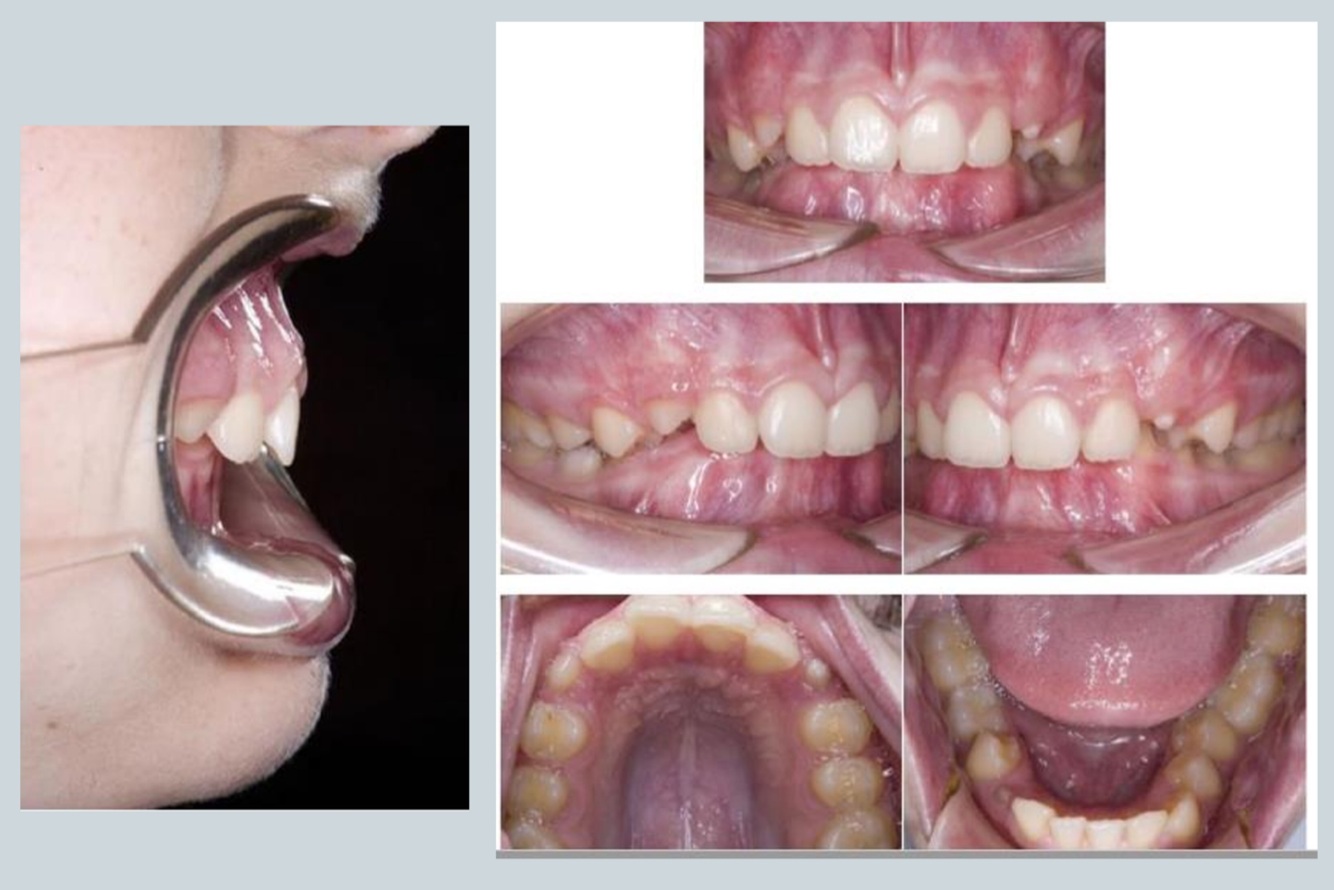

Q

Intra-oral dental examination of class II

22

What can you see - features of CLASS II

A

Well aligned arches

Some teeth need to come through

Classical increase in overjet - cheek retractors show extent of the overjet

23

Mandibular position of class II Div I

Ask pt to bite on back teeth when assessing overjet